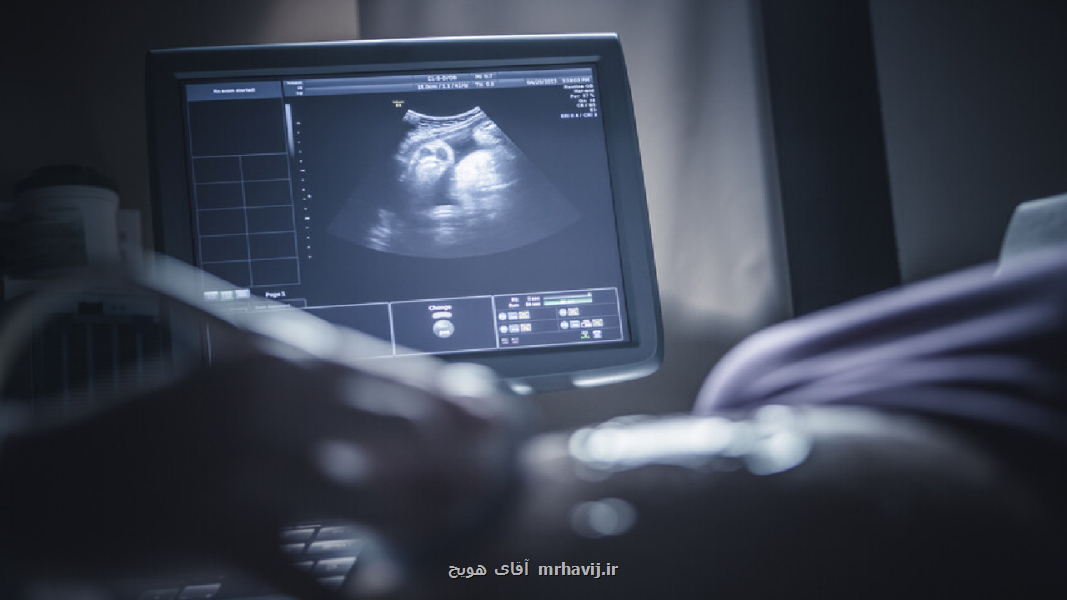

به نقل از ایشان، در ۴ هفتگی قلب بچه با میکروسکوپ قابلیت مشاهده بوده و در هفته هفتم با سونوگرافی قلب بچه قابل دیدن است. بررسی ها نشان داده است که از هفته ۱۴ جنین دارای احساس درد است.